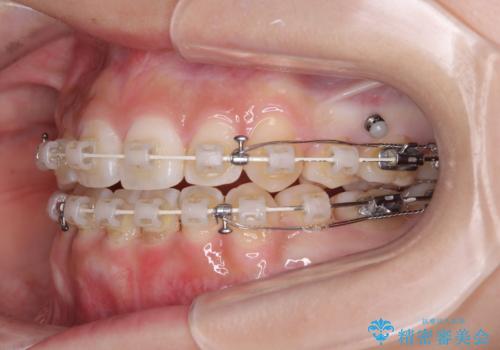

上下非接触の前歯 口元の突出感を改善する抜歯矯正

- 矯正装置

- 審美装置

- 口元の突出感と上下前歯のズレを気にして来院された患者様です。

舌の突出癖により上下の前歯は非接触となっている状態でした。

舌のトレーニングを行わないと上下前歯の接触達成は困難であるため、トレーニングをしっかりと行っていただきながら、治療を進めて行くこととしました。

上下左右の第一小臼歯4本を抜歯し、ワイヤー装置にて矯正治療を行うこととしました。

舌のトレーニングをしっかりと行ってくださり、1年半という非常に短い期間で仕上げることができました。